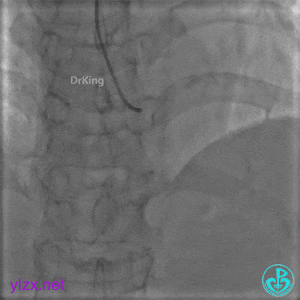

封堵后造影,PL分支远端血流中断。

术后超声未见心包积液。

1周后复查冠脉造影

PL主支通畅,远端一个小分支丢失,未见破口存在。